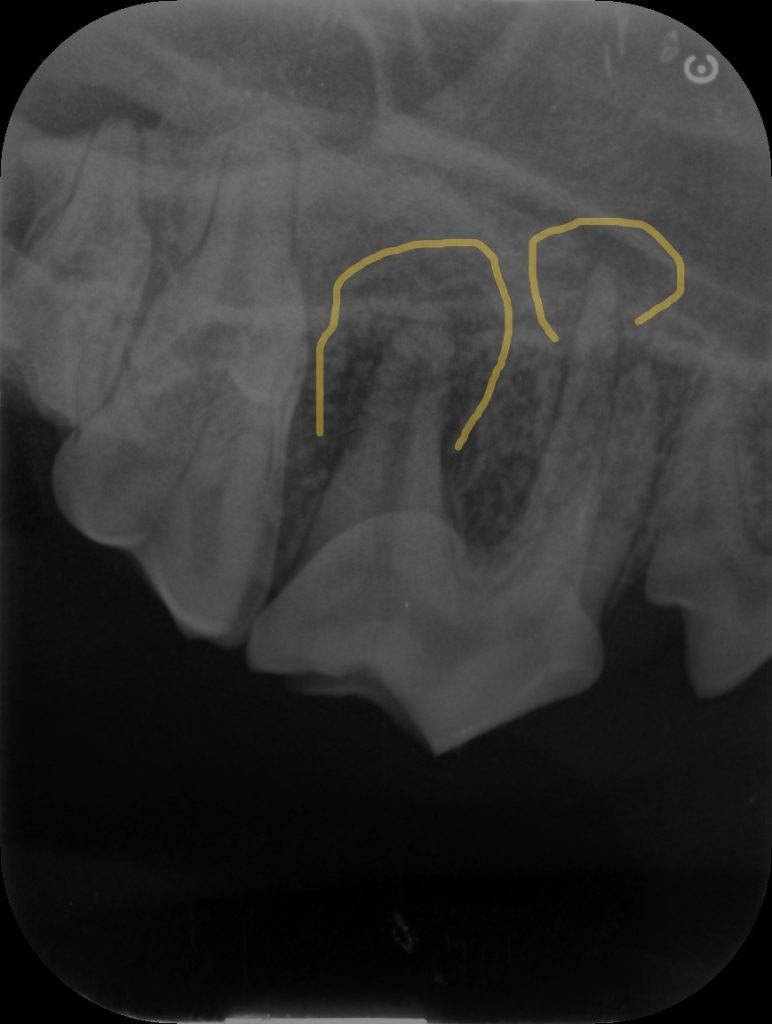

この子もレントゲンを撮影すると

わかりにくいと思いますが、このような範囲で骨が溶けている変化が見られます。

このまま放置をすると顔が腫れたり、膿が出た可能性があります。